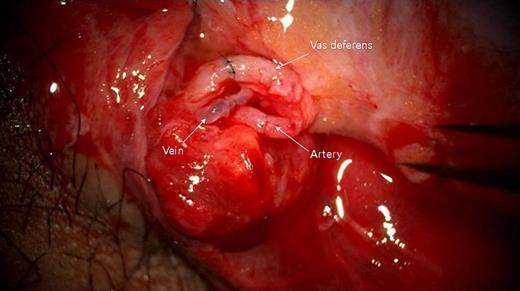

Cooperative surgery was performed by surgeons from the urology and plastic surgery departments. The patient was placed supine in a frog-leg position. The proximal gonadal artery in the spermatic cord was detected easily with pulsating bleeding and secured by clamping without causing vessel injury (Fig. 2). The vas deferens was also found near the gonadal artery with a resilient tactile sense. Thin lumens around the gonadal artery were identified as gonadal veins. The amputated testis was also checked, and the vas deferens was continued from the tail of the epididymis. The gonadal artery was located in the same direction as the vas deferens. The testis was fixed on the scrotal wall to prevent it from roaming freely. The gonadal artery was first connected using 11-0 nylon under an operating microscope (KINEVO 900, Zeiss; Fig. 3). After vein drainage was confirmed, gonadal vein anastomosis was performed with 11-0 nylon (Fig. 3). Lastly, two-layer vasovasostomy was carried out with 8-0 nylon (Fig. 3). After the end-to-end anastomosis of the artery, vein, and vas deferens, the viability of the testis could be confirmed in terms of vascularity on gross and indocyanine green fluorescence perfusion (Fig. 4). The cremasteric muscle of the spermatic cord was reinforced to reduce tension in the anastomosis sites, and orchiopexy was performed to prevent testicular torsion. The other testis was replanted in the same maneuver (right testis: artery 1ea, vein 1ea; left testis: artery 1ea, vein 2ea). The ischemic time of each testis was 7 h (right) and 8.5 h (left). Each testis was raised on a high scrotal area and fixed with the approximated dartos fascia because of the large skin defect of the scrotum (Fig. 5). Lastly, the amputated scrotal wall after defatting was used to cover the whole defect.

Immediate post-anastomosis findings of the right testis. Upper: vas deferens; middle: testicular vein; lower: testicular artery.